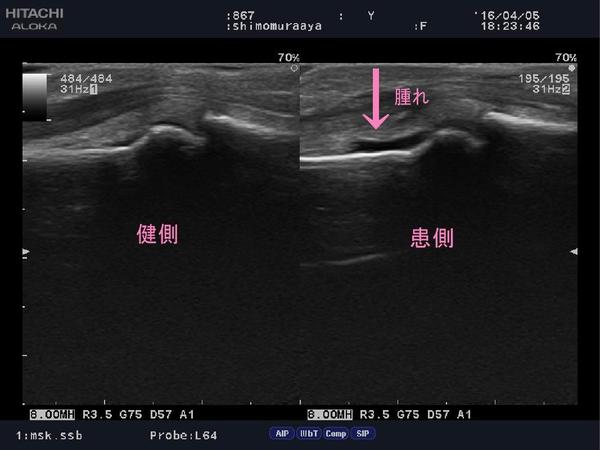

「まる接骨院」では超音波画像観察装置で損傷の有無を確認し、

正確な処置、治療を行って参ります。